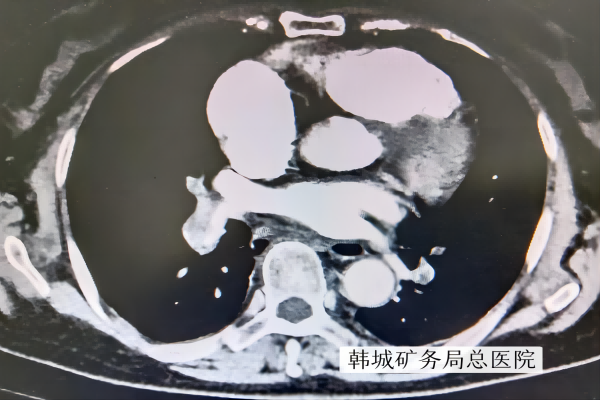

4月18日上午,69岁的孙阿姨被家人搀扶着走进了陕西健康集团韩城矿务局总医院心血管内科,只见她满头大汗,颜面苍白,口唇发紫,医师询问得知,患者最近一段时间,总是稍有活动即感胸闷、气短、心慌、全身大汗,尤其是这几天反复发作,症状明显加重,总感觉全身乏困无力。主管护士陈艳立即扶着患者平躺于床上,心电监护示心率112次/分,血压85/55mmHg,血氧饱和度80%,立即给予面罩吸氧。高亚妮医生为患者进一步检查的同时,让护士抽血急查血凝、血气分析、心肌损伤标志物及脑钠肽,化验D二聚体,均明显高于正常。急行床旁心脏B超提示:右心大伴三尖瓣大量返流,右心整体收缩功能正常,左室舒缓功能减低,肺动脉高压(中度)。行双下肢血管B超提示,双下肢静脉血栓形成,高度怀疑肺栓塞可能。立即上报请示心血管内科主任尹哲,在备好氧气等急救措施情况下由医护人员护送行肺动脉CTA,结果提示右肺动脉干,双肺多发段及亚段级肺动脉栓塞,肺动脉高压。